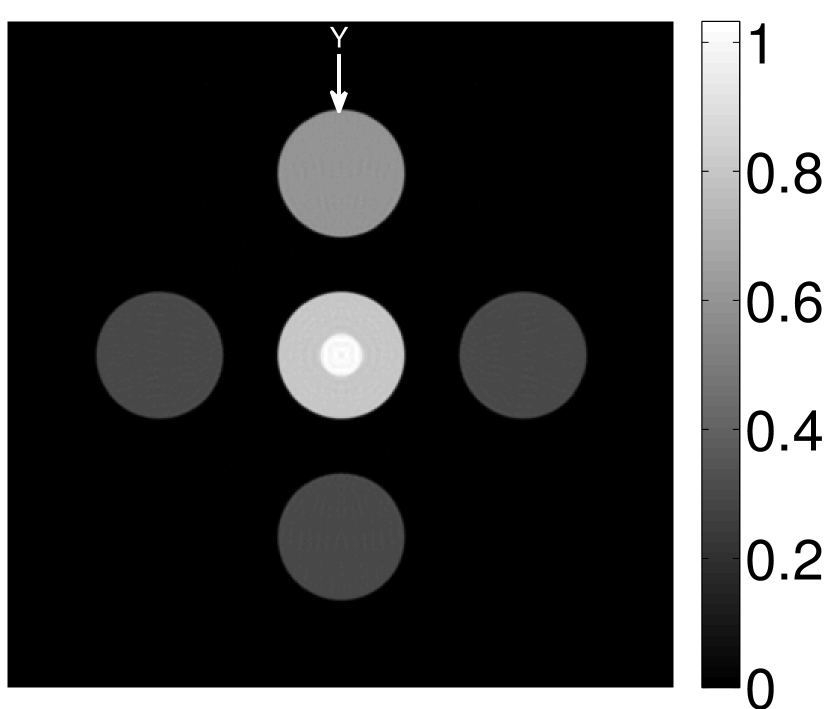

Figure 2(a) shows the image reconstructed by use of the conventional iterative method that utilized a system matrix based on EIR-2. Different values of the regularization parameter from the interval were considered. The reconstructed image with the value of that minimized the RMSE was chosen to represent the best performance of the conventional iterative method. Figure 2(a) and the profile in Figure 2(c) demonstrate that the use of an inaccurate EIR can result in strong artifacts and distortions in images reconstructed by use of the conventional methods.

When the VP algorithm was applied, different values of the regularization parameter from the interval and from the interval were considered. The image that minimized the RMSE was chosen and displayed in Figure 2(b). As revealed by this image and the profiles in 2(c), the VP algorithm yielded an image with fewer artifacts and distortions, and image fidelity was improved as reflected by the reduced RMSE.

Figure 7(a) reveals that use of the inaccurate EIR in the conventional iterative method created strong artifacts and distortions. Figures 7(b) confirms that the artifacts and distortions were significantly mitigated when the VP method was employed. Image profiles for both cases are shown in Figures 7(c). The overall accuracy of the recovered EIR, shown in Figure 7(d) and 7(e), was improved, but it contained spurious oscillations.